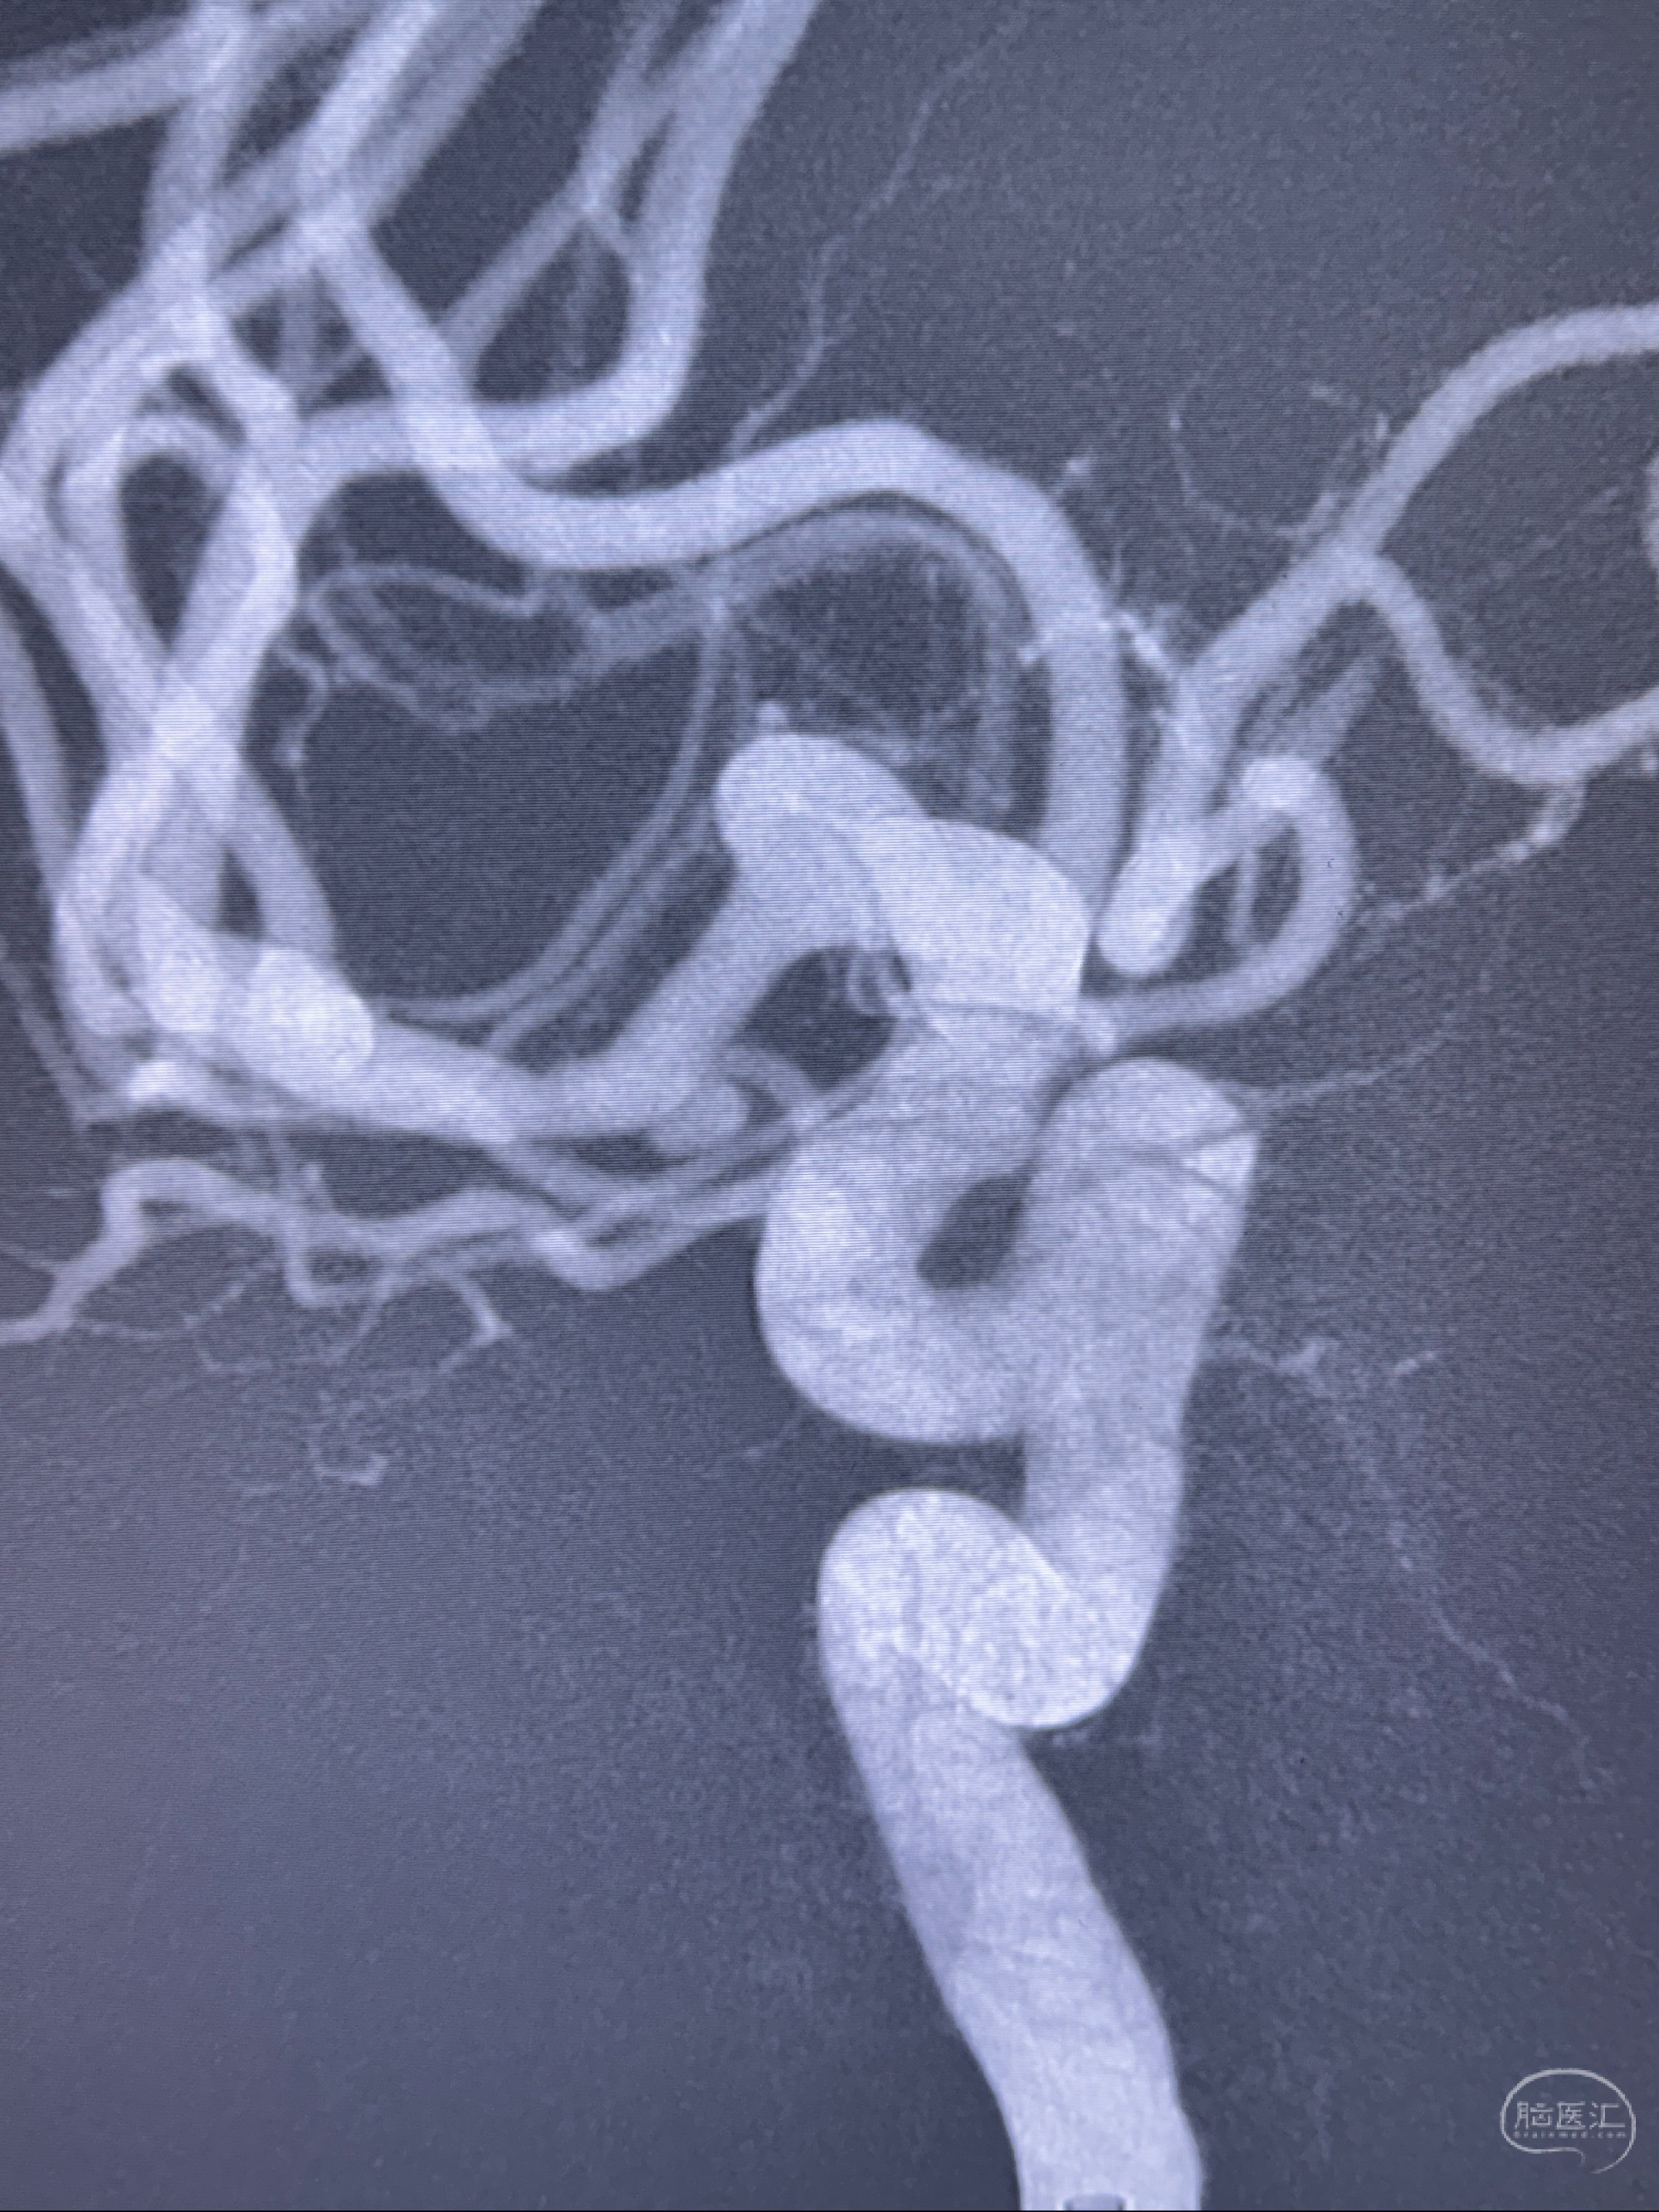

2023-11-24DSA:右侧大脑中动脉下干起始部动脉瘤,约2.3*2.5mm,形态规则

2023-12-04全麻下行支架辅助治疗

S-AB4-20mm

麻醉苏醒佳,遵嘱动作

术后即刻CT